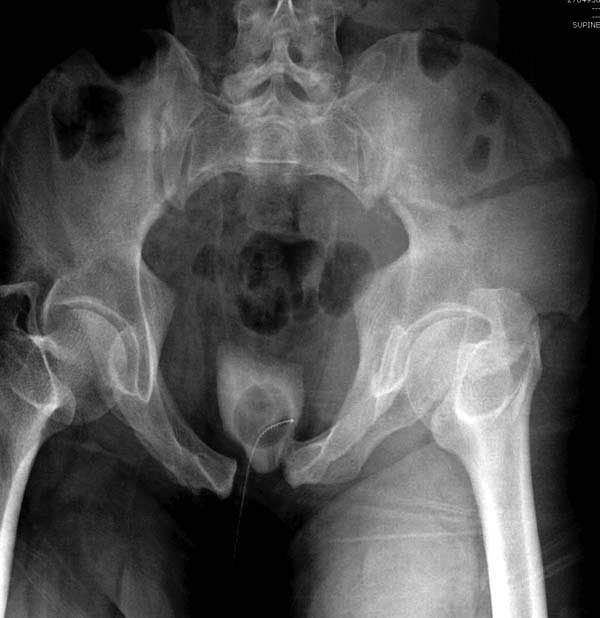

Здесь представлен случай 38 летнего больного (падение с высоты 9 метров) с нарушением тазового кольца. При поступлении для стабилизации передне-нижний аппарат наружной фиксации и на 6й день, вчера, операция из двух доступов.

Представлены снимки техники проведения стержней. Через место прикрепления прямой мышцы в Inferior Iliac Spine в направления вырезки создается жесткость. Weber clamp изнутри таза для репозиции, и фиксация после репозиции перелома крыла подвздошной кости. Наружный аппарат удален, нагрузка предполагается через два месяца.